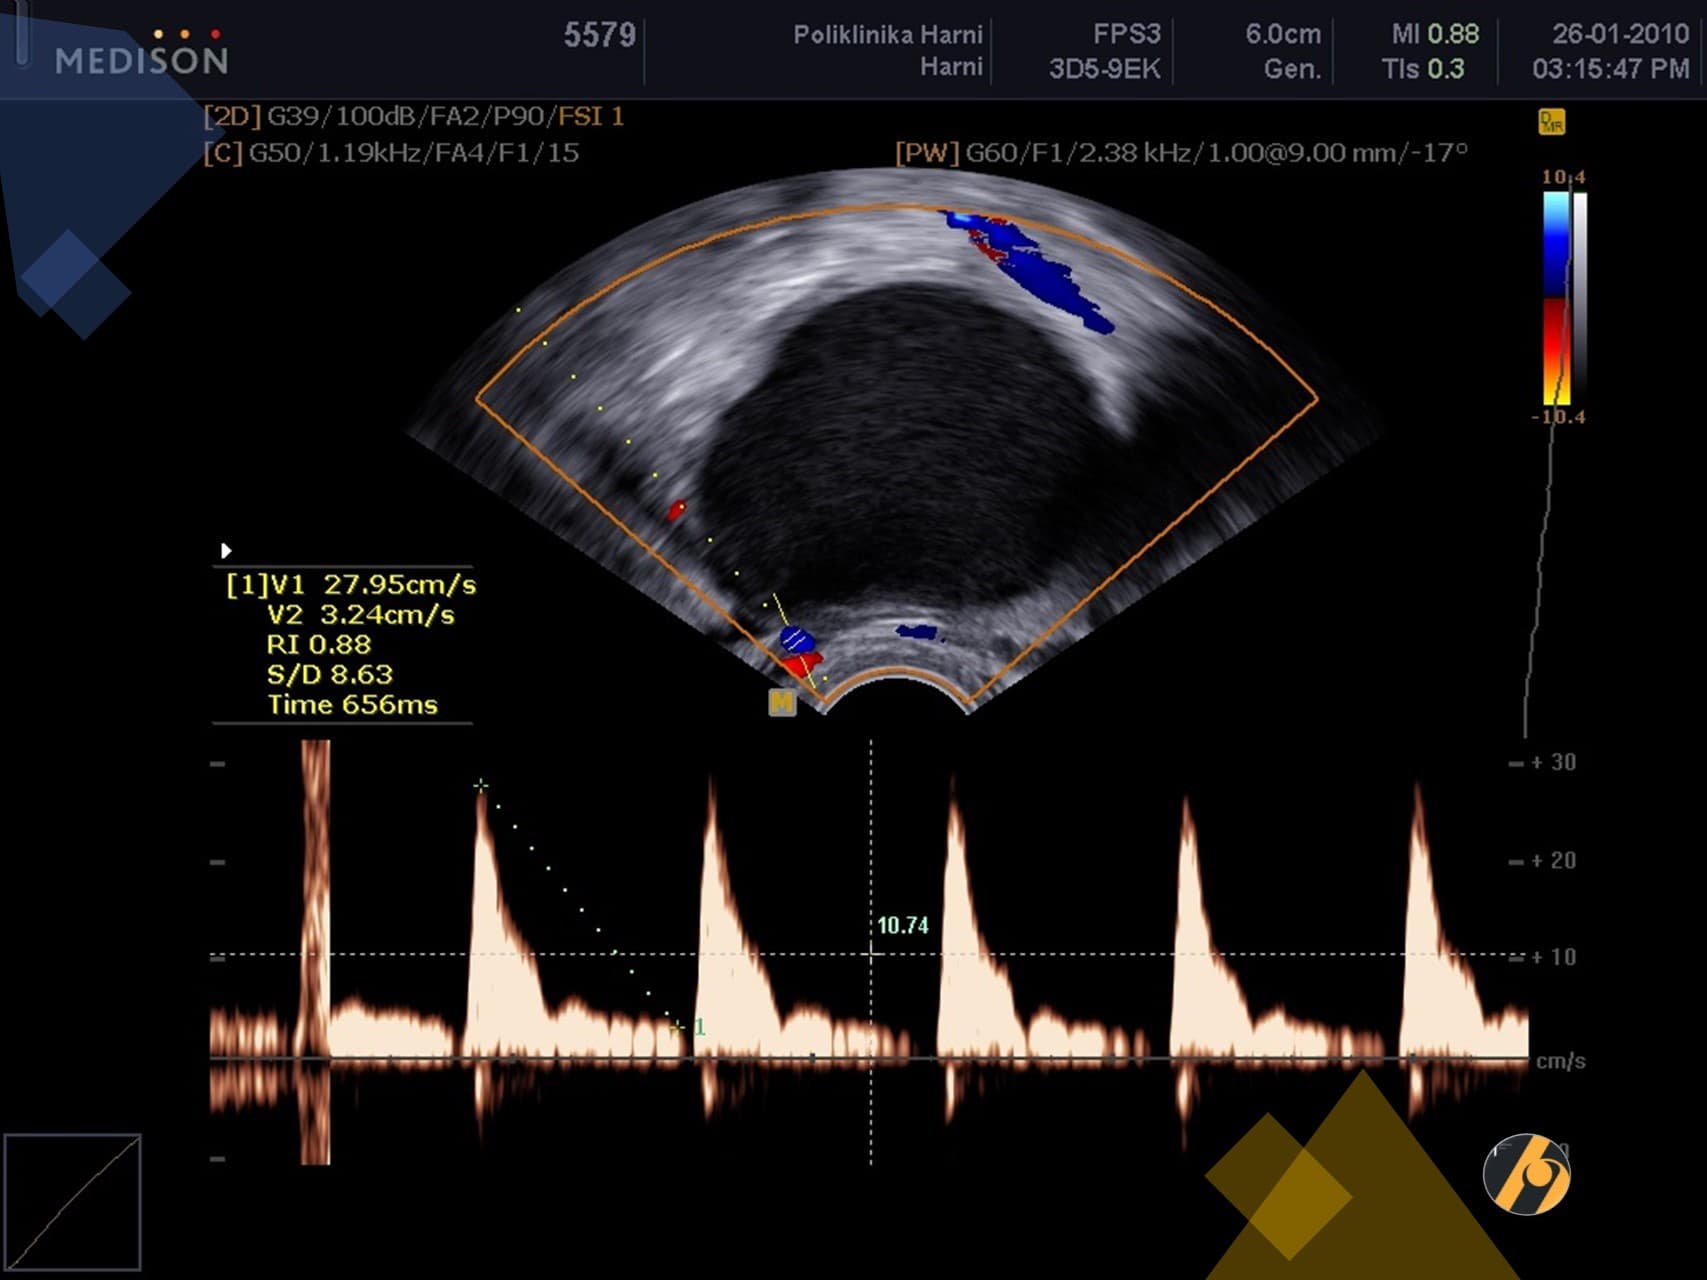

Premda su laparoskopija i patohistološka dijagnostika zlatni standard u dijagnostici endometrioze, u postavljanju dijagnoze od pomoći mogu biti i drugi manje invazivni postupci. Nažalost, ove tehnike kao što su transvaginalna sonografija i magnetska rezonancija nisu u stanju otkriti manje ili lezije koje su manje aktivne. Transvaginalna ultrazvučna dijagnostika učinkovito otkriva endometriotička žarišta čiji je promjer veći od 19 mm (¾ incha).